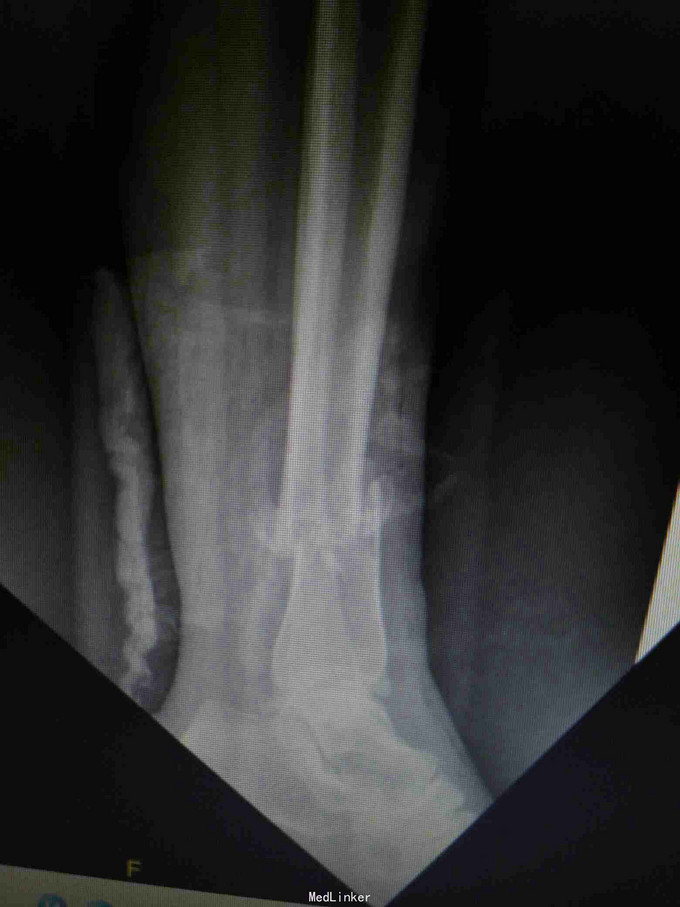

患者,男,29岁,摔伤致左小腿肿痛,活动受限,流血2小时入院。

入院查体:左小腿下段内侧可见一约2cm大小开放伤口,左下肢皮肤感觉及末梢血运正常。

诊断:左胫腓骨下段开放性骨折。 治疗:考虑内侧有开放伤口,行内侧钢板固定感染概率大,我们采用前外侧入路,显露胫腓骨下段骨折端进行固定。